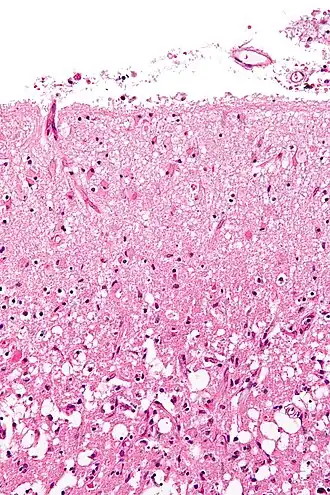

A brain autopsy demonstrating signs of meningitis. The forceps (center) are retracting the dura mater (white). Underneath the dura mater are the leptomeninges, which appear to be edematous and have multiple small hemorrhagic foci.

Various microscopic findings are present at times from infarction as follows:[32]

Histopathology at high magnification of a normal neuron, and an ischemic stroke at approximately 24 hours on H&E stain: The neurons become hypereosinophilic and there is an infiltrate of neutrophils. There is slight edema and loss of normal architecture in the surrounding neuropil.